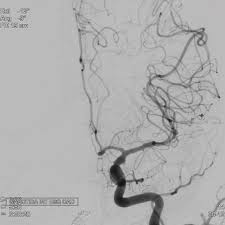

Aneurysm ˈænjəˌrɪzəm n → aneurisma m. We explain the different types of aneurysms, the symptoms you should watch out for, and how one is diagnosed. Daselbst) oder in ihrer umgebung vorkommende, in ihrem innern blut enthaltende, geschwulst, welche entsteht entweder durch theilweise erweiterung der höhle einer arterie, (wahre… … Because of the constant pressure of the circulating blood within the artery, the weakened part of the arterial wall becomes enlarged, leading ultimately to serious and even fatal. Un aneurisma è un rigonfiamento di un'arteria causato da un infortunio oppure dall'indebolimento delle pareti vascolari.1 x fonte attendibile national heart, lung, and blood institute vai alla fonte si può formare in qualunque parte del corpo, ma è più comune nell'aorta (l'arteria principale che proviene dal. Learn about detection, diagnosis, treatment options and advances for brain aneurysm, including surgical clipping, endovascular coiling and flow diverters. Un aneurisma es una pequeña protuberancia con forma de globo y llena de sangre que se forma en las paredes de los vasos sanguíneos. See more of aneurisma on facebook. Explicamos sus riesgos para evitarla. Un aneurisma es la dilatación de las paredes de una arteria que puede romperse y provocar una hemorragia. Esta dilatación aparece en una zona debilitada de la pared. Un aneurisma es una dilatación patológica de un segmento de un vaso sanguíneo, normalmente se produce a nivel arterial. Artärbråck c, pulsåderbråck c, aneurysm c.

Stream tracks and playlists from aneurisma (oficial) on your desktop or mobile device. Coinvolge il grande vaso che trasporta il sangue arterioso, ricco di un particolare tipo di aneurisma cerebrale, conosciuto come aneurisma a ciliegia, tende a formarsi sulle principali arterie che irrorano il cervello. Learn about detection, diagnosis, treatment options and advances for brain aneurysm, including surgical clipping, endovascular coiling and flow diverters. Un aneurisma es un ensanchamiento o abombamiento anormal de una parte de una arteria debido a debilidad en la pared del vaso sanguíneo. We'll also explain how to prevent and treat aneurysms. The exact cause of an aneurysm isn't clear, but certain factors can contribute to developing one, such as high blood pressure. See more of aneurisma on facebook. Es una dilatación localizada y permanente que se produce en las paredes de las arterias, localizándose en los distintos tramos de la vena aorta. Artärbråck c, pulsåderbråck c, aneurysm c. Cualquier vaso puede presentarlo pero es más común en la arteria aorta, los vasos cerebrales, la arteria poplítea, la arteria mesentérica y la arteria esplénica. Inflamación anormal llena de sangre en una arteria o una vena, como resultado de una debilidad muscular localizada en la pared del vaso. Un aneurisma es la dilatación de las paredes de una arteria que puede romperse y provocar una hemorragia. An aortic aneurysm is a bulge in the main vessel that supplies blood to your body.